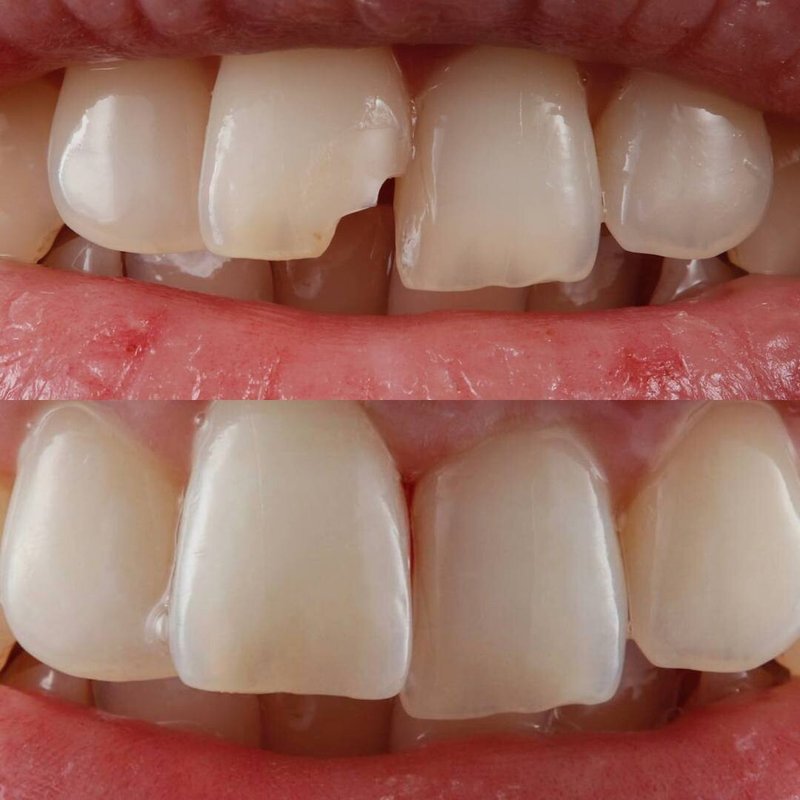

Фотогалерея

Занимается эстетической реабилитацией улыбки путем отбеливания, художественной реставрацией и виниров, а также лечением таких заболеваний, как кариес, пульпит, периодонтит, гингивит, гиперестезия, флюороз и др.